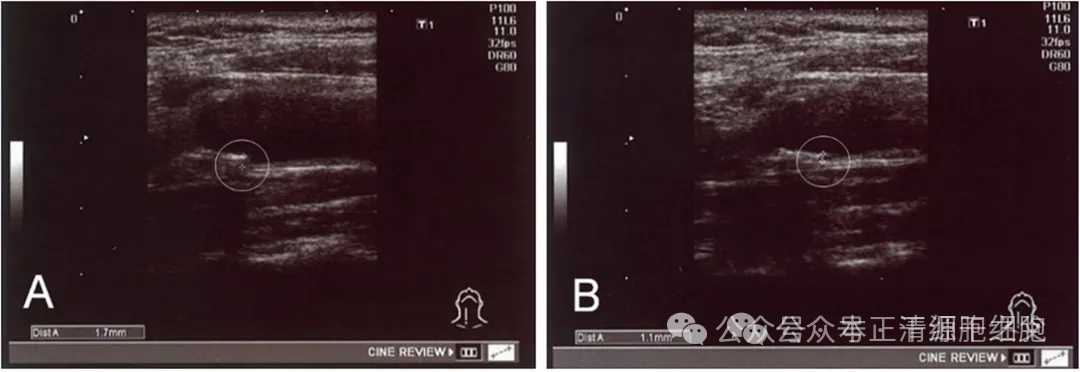

在治疗前 HDL 值异常的12 名患者中,11 名(91.7%)的值有所改善。总体而言,治疗后的测量值与治疗前相比显着增加(p <0.01)。此外,在治疗前LDL 水平异常的 8 名患者中,有 6 名(75%)在治疗后发现 LDL 胆固醇水平下降。在绝大多数 RLP 水平异常的病例中也是如此,28 例中有 24 例(85.7%)水平下降。18 例治疗前 IMT 值异常的患者, 治疗后 IMT 值显着下降(p < 0.01)。其中,一名 56 岁男性患者在 MSC 治疗前 ( a ) 和治疗后 ( b ) 的颈总动脉 IMT 示例显示,治疗后近 4 个月,IMT 从 1.7 毫米下降至 1.1 毫米。总结:近10年临床试验证实,干细胞可以减轻内皮功能障碍、降低血清脂质水平、抗炎并稳定现有的动脉粥样硬化斑块,这使得其成为有效干预动脉粥样硬化疾病研究的理想选择。随着对干细胞临床治疗的进一步研究,相信未来将造福更多动脉粥样硬化患者。